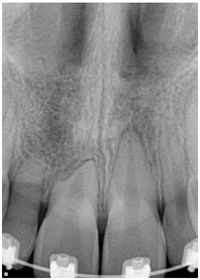

Impacted Canine Xray - Jason ErasmusImpacted canines and teeth that are left in place may go throughout the patient’s lifetime with no untoward effects. However, close monitoring and at regular dental care intervals is recommended. On the other hand, these impacted teeth may have several untoward effects and consequences.